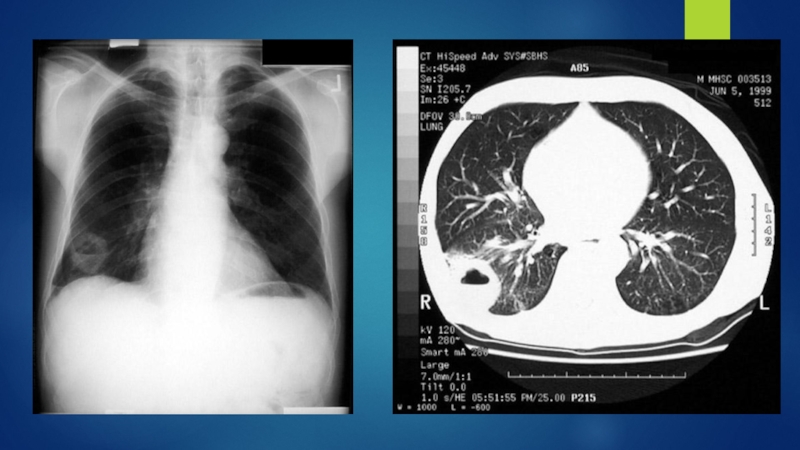

Слайд 20Диагностика

Сбор жалоб, анамнез.

Данные объективного исследования.

Рентгенография:

инфильтрат в легком

расширение средостенья

ателектаз

плевральный выпот

Бронхоскопия

Цитологическое исследование

мокроты

С целью определения степени распространенности процесса производят: КТ органов грудной

полости и верхнего этажа брюшной полости (печень, надпочечники), КТ с контрастированием, МРТ, ПЭТ/КТ, сцинтиграфия костей, КТ или МРТ головного мозга.

ДиагностикаСбор жалоб, анамнез.Данные объективного исследования.Рентгенография:инфильтрат в легкомрасширение средостеньяателектазплевральный выпотБронхоскопияЦитологическое исследование мокротыС целью определения степени распространенности процесса производят: